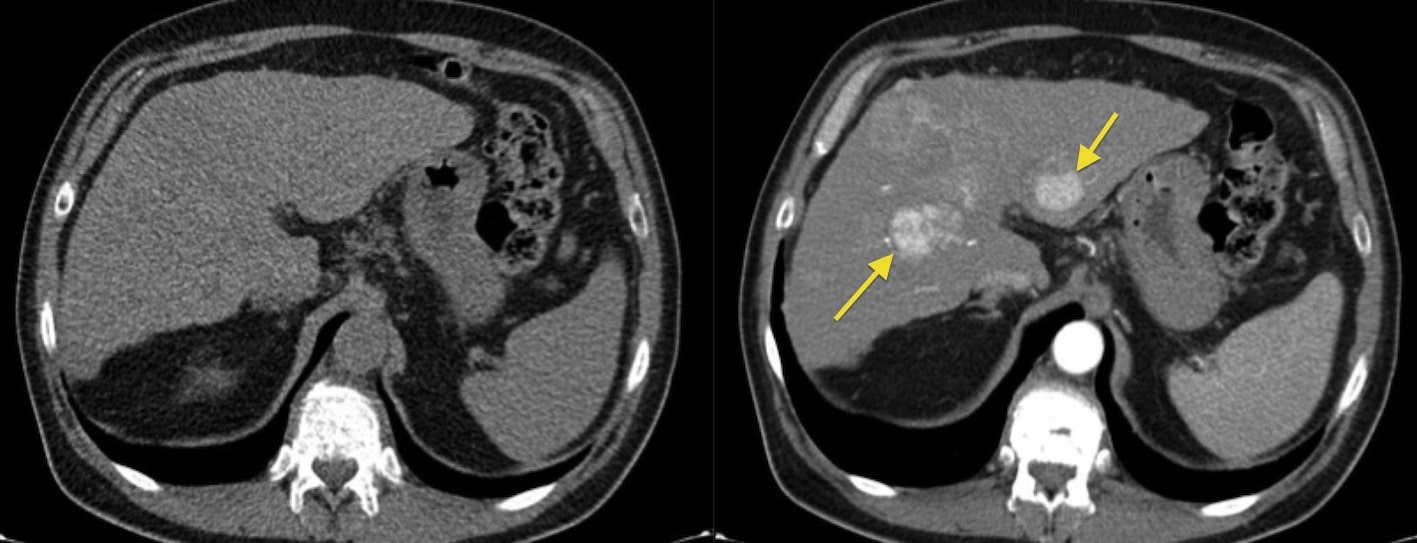

Одной из основных причин назначения КТ с контрастом являются подозрения на наличие опухолей. Контраст помогает обнаружить новообразования, которые не всегда видно при стандартной КТ. Кроме того, он используется для оценки степени воспалительных процессов, таких как аппендицит или панкреатит, когда требуется детальный осмотр пораженных тканей.

- Контраст помогает в выявлении опухолей, воспалительных процессов и аневризм, которые могут быть скрыты при обычном исследовании.

- Без контраста диагностическое исследование может не выявить ранние стадии заболеваний.